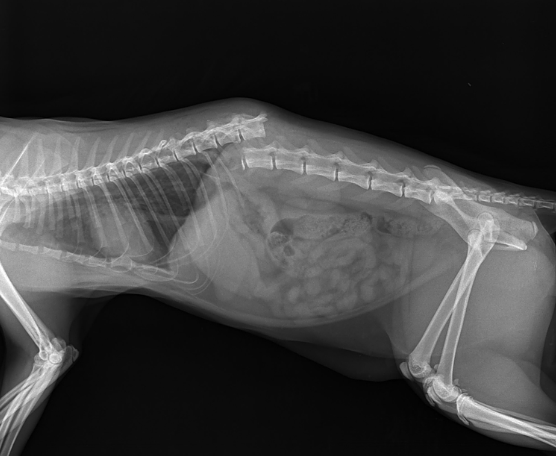

Перелом позвоночника, полученный при падении с большой высоты

Наиболее частыми повреждениями при падении с большой высоты являются различные переломы. К наиболее серьёзным последствиям ведут переломы позвоночника, в результате которого у кошки возникают парезы или полный паралич тазовых конечностей.